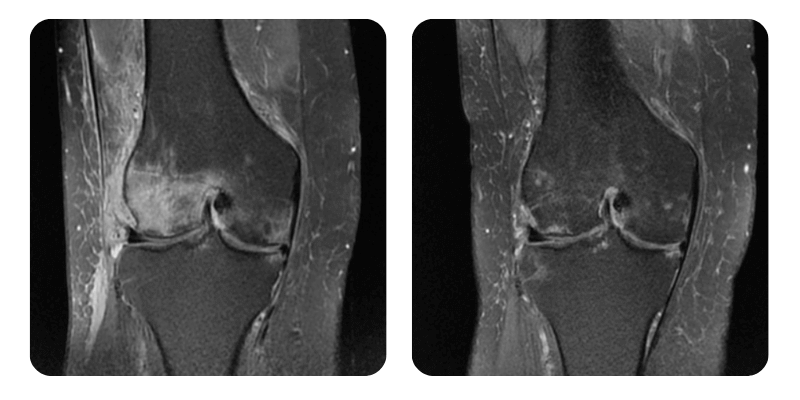

Prima

Dopo

64 anni - Necrosi asettica del condilo femorale esterno destro.

Anamnesi: Paziente di 64 anni con necrosi asettica del condilo femorale laterale destro, che si presenta in clinica con dolore 5/10 al ginocchio destro, insorto da circa 2 mesi. Nessun antecedente personale rilevante.

Diagnosi: Necrosi asettica del condilo femorale esterno destro.

Evoluzione: Al controllo, dopo un ciclo di 20 sedute, la paziente riferisce riduzione del dolore a 2/10, non più continuo, con mobilità aumentata.